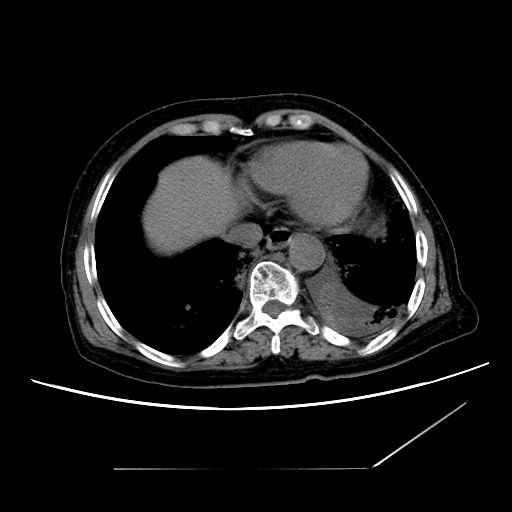

标题: CT25393:病人45岁,咳嗽,吐黄痰带血丝,发热,胸闷月余 [打印本页]

标题: CT25393:病人45岁,咳嗽,吐黄痰带血丝,发热,胸闷月余

1、左肺中央型肺癌并双肺弥漫性转移   2、双肺部感染    3、肺大泡     4、左侧胸腔积液

双侧肺弥漫性病变,可见“空泡征”及“蜂窝征”,考虑肺泡癌可能性大,左侧胸腔积液,考虑胸膜受累可能!

1)不排除肺泡癌可能。2)左侧胸腔积液。